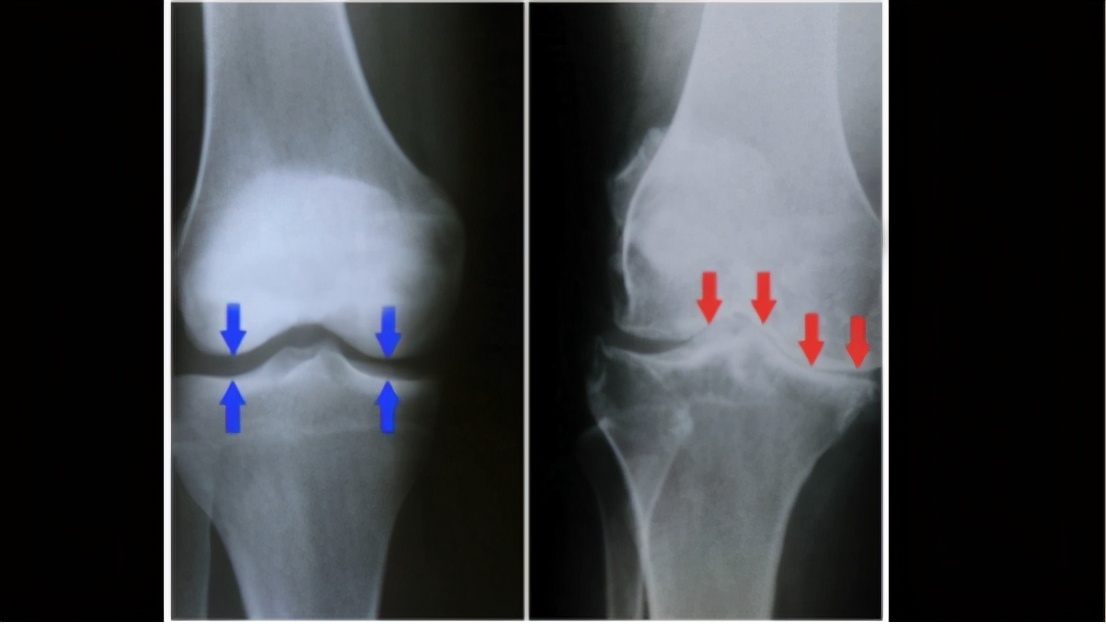

现在两张图一张正常,一张有毛病。正常的骨头中间有空隙就是软骨,年纪大了之后经常活动,软骨被磨损越来越薄,最后被磨掉。剩下骨头碰骨头的时候,就会发生疼痛、肿胀。关节活动不灵活就好像两个东西磨在一起,是正常的磨损,所以会导致关节炎和关节疼痛。 软骨组织的磨损在承重关节上尤其明显,要承担重量。再比如膝盖关节和臀部骨头的关键是要承担上升的重量,越是承重的关节越容易软骨组织磨损。软骨组织磨损在大多数人里面都会有。在日本有个统计超过40岁的人里面,有42%的男性和62%的女性软骨组织的磨损导致关节痛。